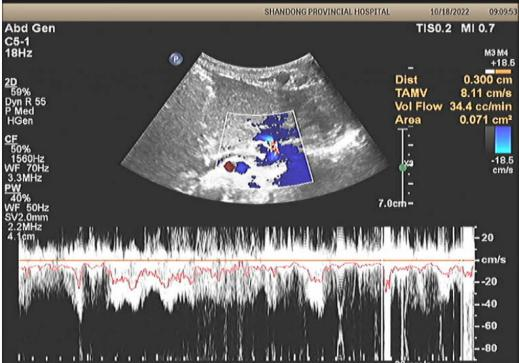

术前血管超声

医学影像科通过CT三维重建获得了清晰的影像,明确了先天性门体静脉分流的类型。该患儿门脉主干发育较细,门静脉左支发育良好,右支纤细,主干侧壁有一粗大的分流静脉,沿肝左叶缘-胃间隙向左上方迂回走行,在近膈肌顶处向下折返,与左肾静脉汇合后汇入下腔静脉,最宽处约7.1mm,最窄处约4.2mm,超声测量分流量约43cc/min,为先天性肝外型门体静脉分流(Abernethy Ⅱ 型)。小儿重症医学科、小儿心脏科通过精心治疗,成功纠正了心动过速、低血糖、高血氨、肺动脉高压、呼吸困难等情况。同时,小儿外科在吴荣德主任的主持下,多次组织讨论,制定了详细的手术方案和预案。患儿治疗23天后顺利出院。

患儿入院后,小儿外科联合小儿重症医学科、医学影像科、超声医学科、麻醉手术科制定了详细的治疗方案。医学影像科马睿主任医师、李宁副主任医师通过CT三维重建获得了清晰的异常血管走形图像,超声医学科王铁铮副主任医师明确了异常分流血管的位置和分流量。小儿普外科团队进行了充分的术前讨论,制定了详细的手术方案和预案。